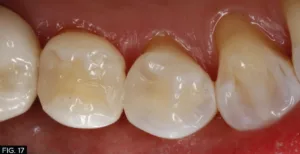

These simple steps demonstrate that once the occlusal pattern and morphology has been created, the restoration can be refined very quickly to obtain the smoothness and luster of natural tooth structure, that it is visibly undetectable to the eye even at the magnification of these photos (FIG. 16, 17). The key to Evanesce Bulk Cure seamlessly blending into the remaining tooth structure lies in the fact this composite has an opacity similar to natural tooth structure. The dual-cure chemistry ensures complete polymerization, in contrast to light-cure composites which require a layered placement technique because the material opacity and cavity depth can limit polymerization.

Final restoration of tooth #28 (#44). Note the seamless blending into the remaining tooth structure and the final luster that has been achieved.